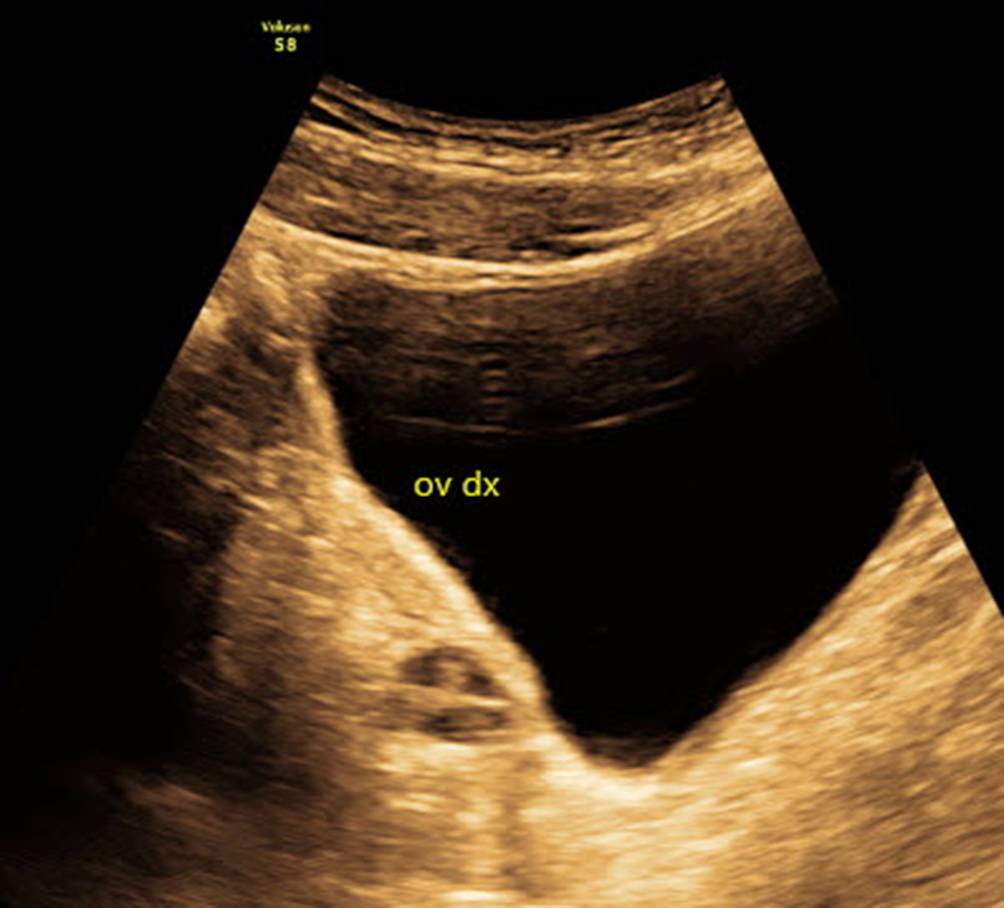

Abb. 12

Normales Ovar einer 13-jährigen Patientin, die mit Verdacht auf PCO zugewiesen wurde, im Abdominalschall